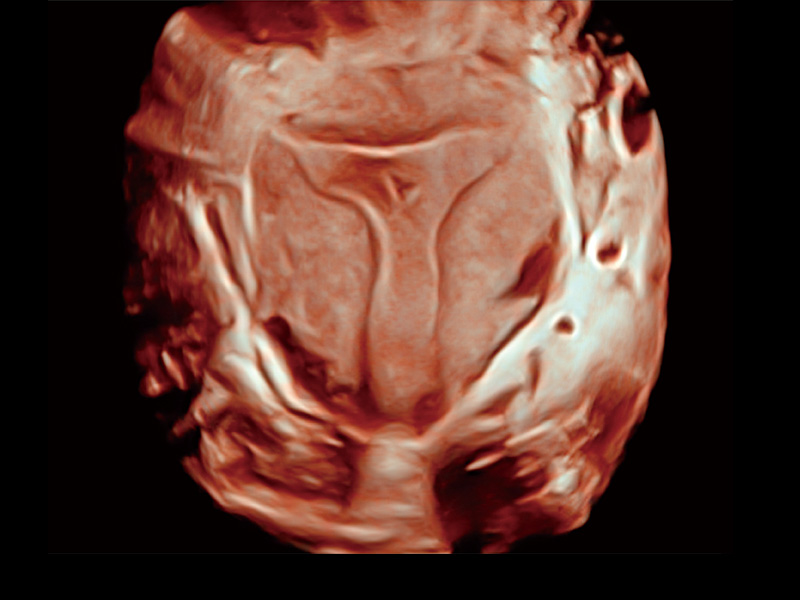

“生育问题”即关系民族复兴,也关系亿万家庭的幸福。随着婚育年龄推迟、社会压力增加等因素,越来越多人群也面临着“生不出、生不好”的问题。辅助生殖作为治疗不孕不育最有效的方法之一,也逐渐成为育儿新希望。而超声检查能为生殖需求人群的初诊评估提供宝贵的信息。 P20 Elite是百老汇电子游戏官网匠心打造的一款生殖应用型彩超。她继承百老汇电子游戏官网高端极光平台,突破性地将多款新型芯片及硬件模块进行整合,均衡了高端系统性能与小巧灵动机身。P20 Elite卓越的图像质量搭载专科探头,旨在为您提供全面的辅助生殖解决方案。

P20 Elite配备了丰富的生殖探头群和临床应用功能,在卵泡监测、穿刺取卵、胚胎移植、妊娠确认等领域,为生殖需求人群提供了新的临床机会,重新定义高端超声如何应用于生殖健康检查。